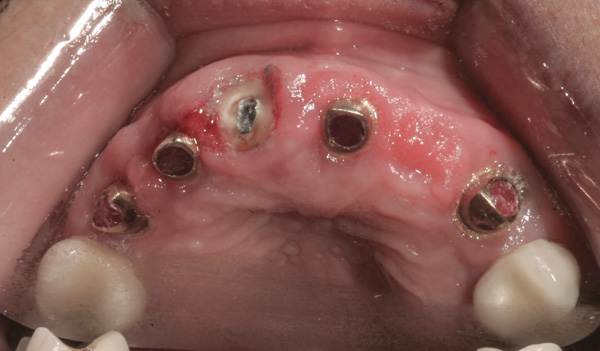

Background: In this case, the patient had a failing mandibular and maxillary dentition due to caries secondary to radiation-induced xerostomia. The patient had had a radical neck dissection to remove a squamous cell carcinoma of the throat 9 years prior to his prosthodontic consultation with the authors. The patient reported a history of radiation therapy following surgery, but did not have a shielding stent. A staged approach was used so as to avoid removable prosthetics on his severely dry soft tissues. He chose to treat his mandibular issues first. Figure 9 shows healing abutments next to the temporarily retained natural teeth, and Figure 10 shows the first-stage custom abutments inserted with relatively good gingival contour and no recession. Recession was clearly seen around all first-stage abutments following adjacent extractions and second-stage implant placement (Figure 11).

Figure 11 Recession evident around first-stage abutments following adjacent extractions and second-stage implant placement.

Figure 11

Figure 12 Remilled and new custom abutments.

Figure 12